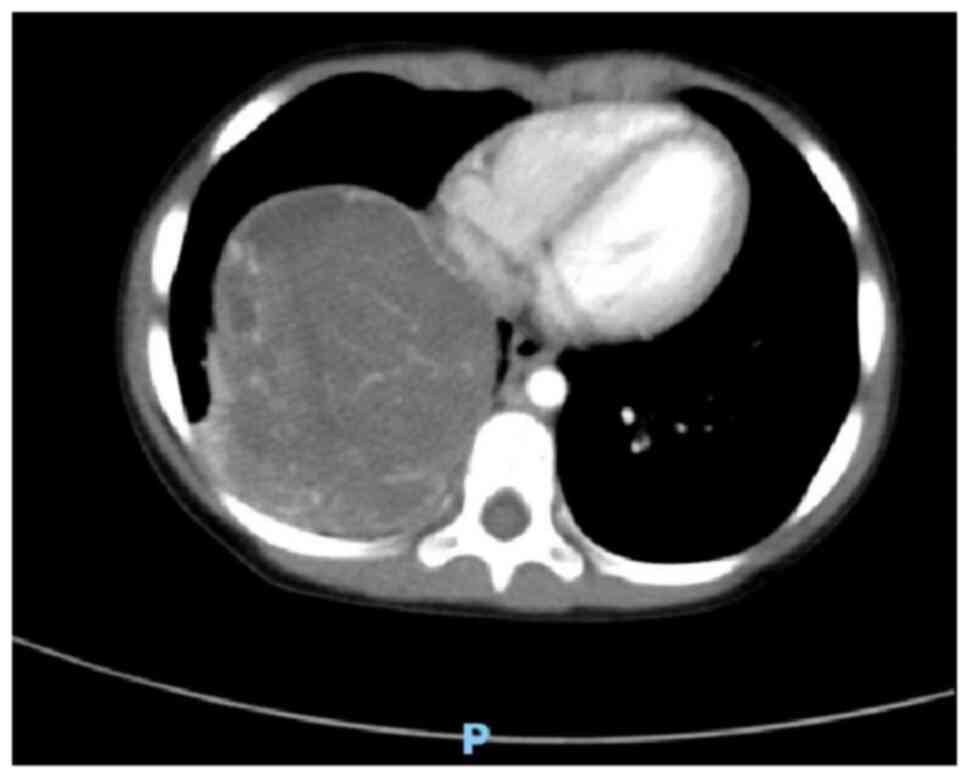

A 3-year-old female patient was admitted to the Affiliated Hospital of Zunyi Medical University (Zunyi, China) in May 2023 for further evaluation after presenting with a 2-month history of cough without obvious inducement and without symptoms including sputum, fever, chills, shortness of breath, dyspnea, abdominal pain, abdominal distension, nausea, vomiting, urinary frequency, and urgency. The symptoms had not markedly improved after oral anti-inflammatory treatment. A chest X-ray revealed bronchitis and a mass in the right thoracic cavity (data not shown), prompting a recommendation for a contrast-enhanced chest computed tomography (CT) scan. Physical examination showed a good mental state, no evident three concave signs, a stable and regular breathing rhythm, symmetrical thorax bilaterally, no pleural friction rub and no subcutaneous crepitus. The right lung exhibited hyperresonance with distinct fine moist rales. A chest CT plain scan and enhanced scan revealed a mass measuring ~85×74×68 mm in the right lower thoracic cavity with uneven density, clear boundaries, and significant heterogeneous enhancement on the contrast-enhanced scan (Figs. 1 and 2). Multiple tortuous vascular shadows were noted within the mass. The right lower lobe was compressed, and flaky increased density shadows were observed in the right middle and lower lobes. The mediastinum remained centered, with no enlarged lymph nodes in the mediastinum or bilateral pulmonary hila. The size and morphology of the heart appeared normal. These findings indicated a space-occupying lesion in the right thoracic cavity, which was considered a neoplastic lesion likely representing PPB.

Figure 2.

Chest CT enhancement shows uneven and obvious enhancement of the lower right thoracic mass.

Imaging examinations, particularly chest CT scans, are valuable in differentiating the characteristics of lung lesions. These scans can not only identify the heterogeneity of PPB but also provide diagnostic insights into the presence of pleural effusion and chest wall invasion. For larger masses, a biopsy can be performed under CT guidance to confirm the diagnosis (15). In the present case, CT revealed a right lung mass identified as a neoplastic lesion, possibly indicative of PPB. Differentiation between neurogenic tumors and germ cell-derived tumors is necessary and should be corroborated with clinical and pathological findings. Typically, PPB presents as a solitary, well-defined mass that can exceed 10 cm (13). Based on histological variations, CT scans display different imaging characteristics. Type I PPB lesions often appear as single or multiple subpleural or intrapulmonary cystic masses, requiring differential diagnosis from other cystic lesions such as bronchogenic cysts, pulmonary cysts, pulmonary bullae and interstitial emphysema. Type II PPB frequently presents as intrapulmonary cystic and solid masses, whilst type III PPB predominantly manifests as solid lesions with uniform density and clear boundaries. The differential diagnosis of type II and III PPB, especially when locally invasive, often necessitates differentiation from other malignant tumors, such as neuroblastoma, Ewing's sarcoma and rhabdomyosarcoma. Although CT provides valuable reference data for clinicians and pathologists in diagnosing PPB, it is not definitive, and the final diagnosis relies on pathological examination (3,4).